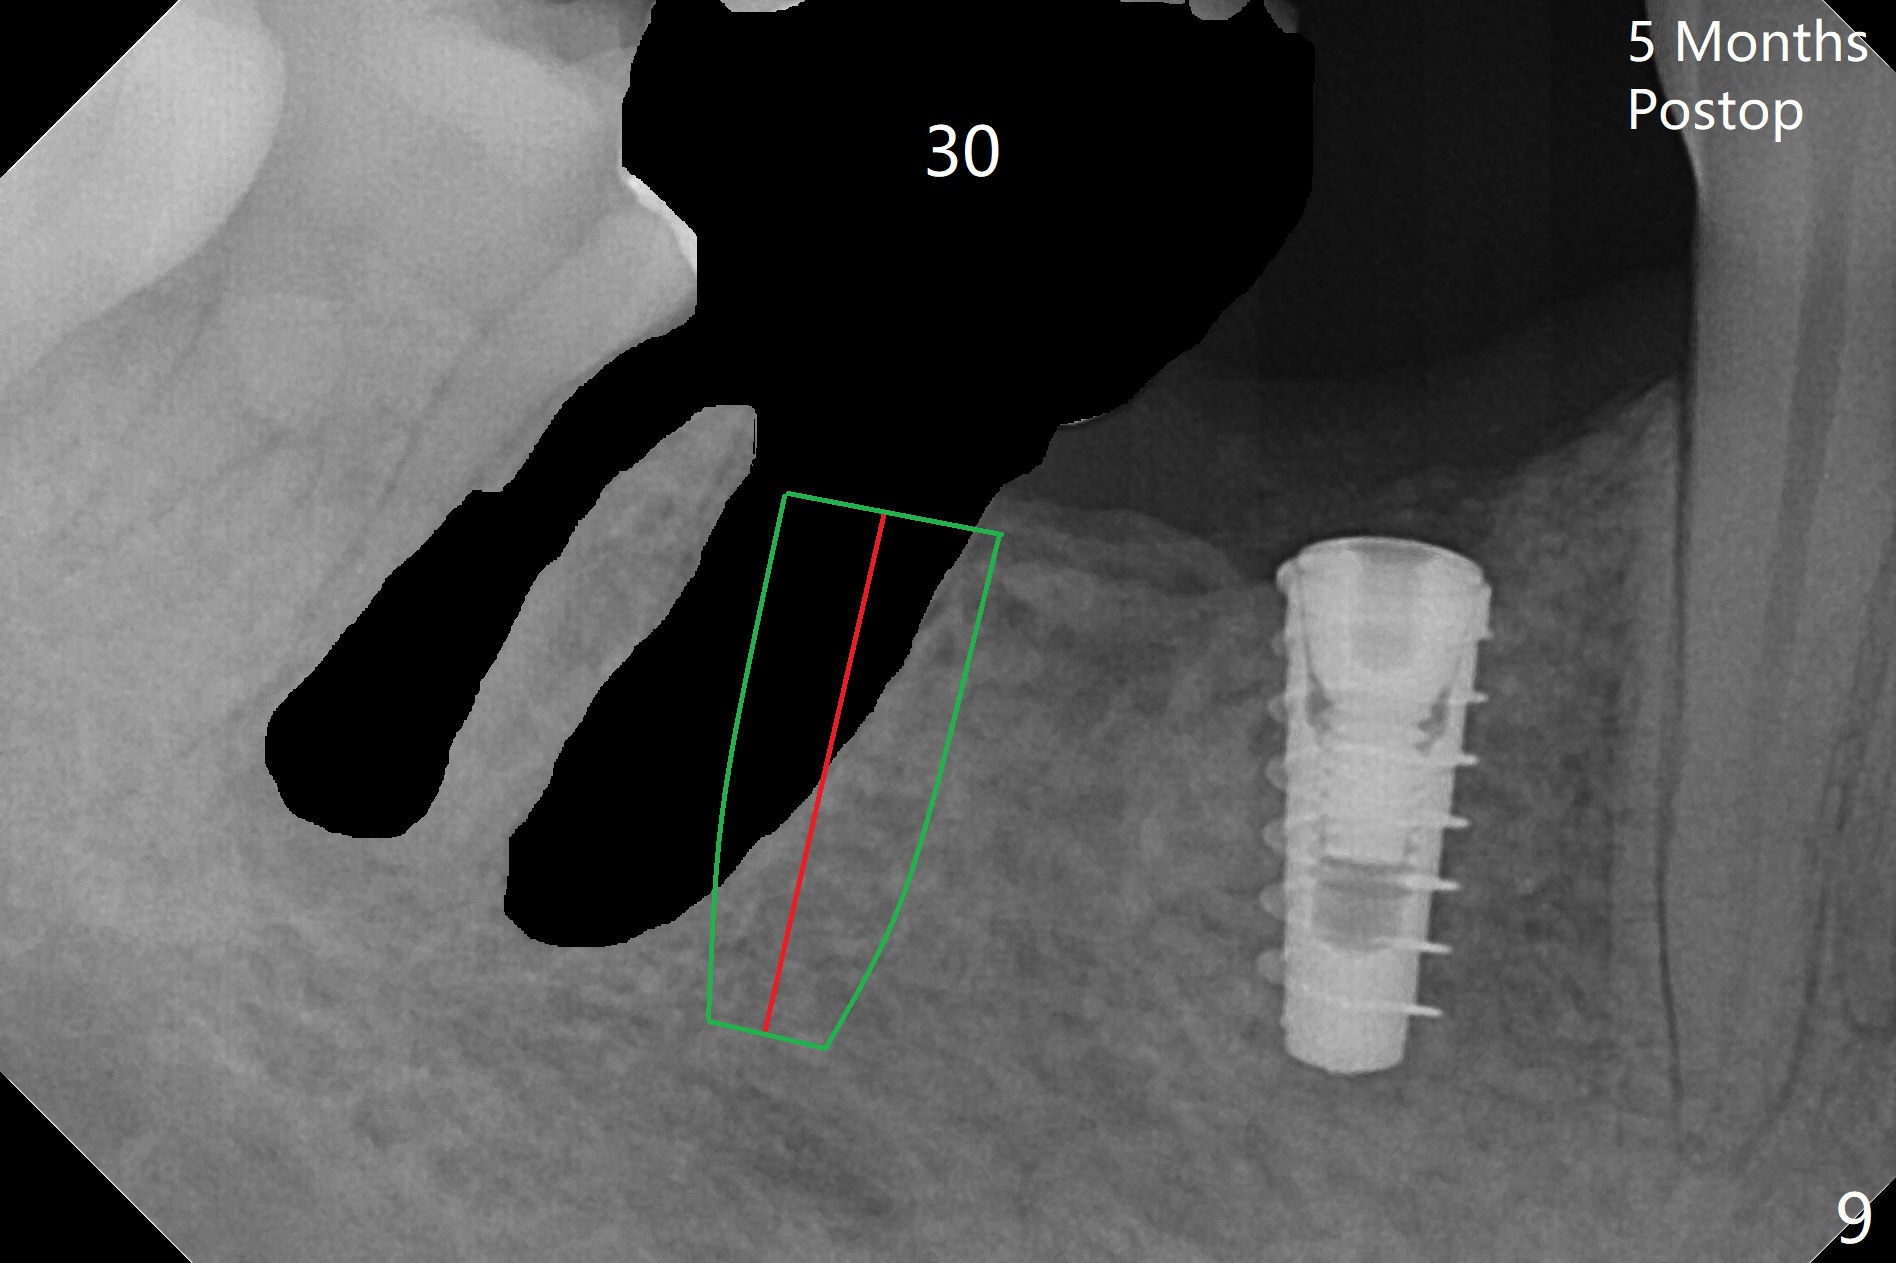

The patient returns for implant placement 11 months post extraction of #28 and 29. With flapless manner, initial osteotomy happens to drop into the original socket of #28 (Fig.4). After use of 3.3 mm Magic Drill (MD) and Final Drill for 15 mm, a 4x11 mm dummy implant is placed (Fig.5). It appears that the implant is long for the site (red dashed line: Mental Loop). However, a definitive implant (4x9 mm, IBS) has difficulty to reach its depth (Fig.6). After several rounds of untorque and retorque, the implant does not seat completely (Fig.7, implant driver disengagement) with autogenous bone placed distal (>). Retrospectively, a larger MD should have been used (3.8 mm) for complete seating in the dense bone. In fact she is post breast cancer treatment with 50% chance of relapse. The patient returns for follow up 1.5 months postop (Fig.8). The wound has healed. Impression is taken 5 months postop (Fig.9). When the crown is cemented, food impaction is an issue between the implant crown and crown at #30. Since the tooth #30 is mesially tilted with distal open margin and apical infection, the tooth will be extracted. Osteotomy is going to be initiated in the mesial slope of the mesial socket (Fig.9 red line). An implant will be placed more or less in the mesial socket (green box).